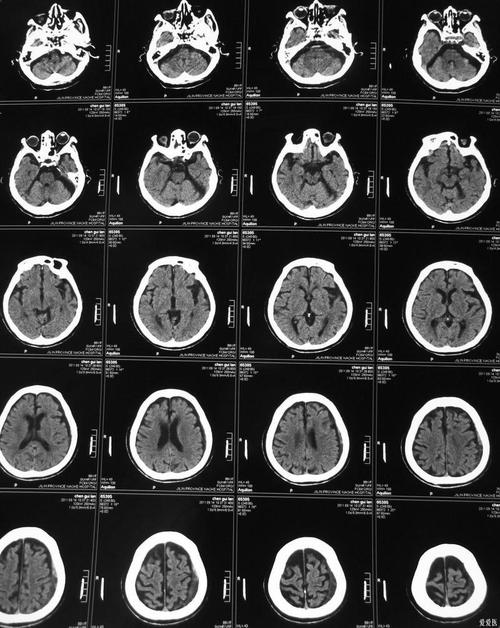

(图片来源网络,侵删)

- 病灶小: CT上显示的梗塞范围很小,可能只是一个小点。